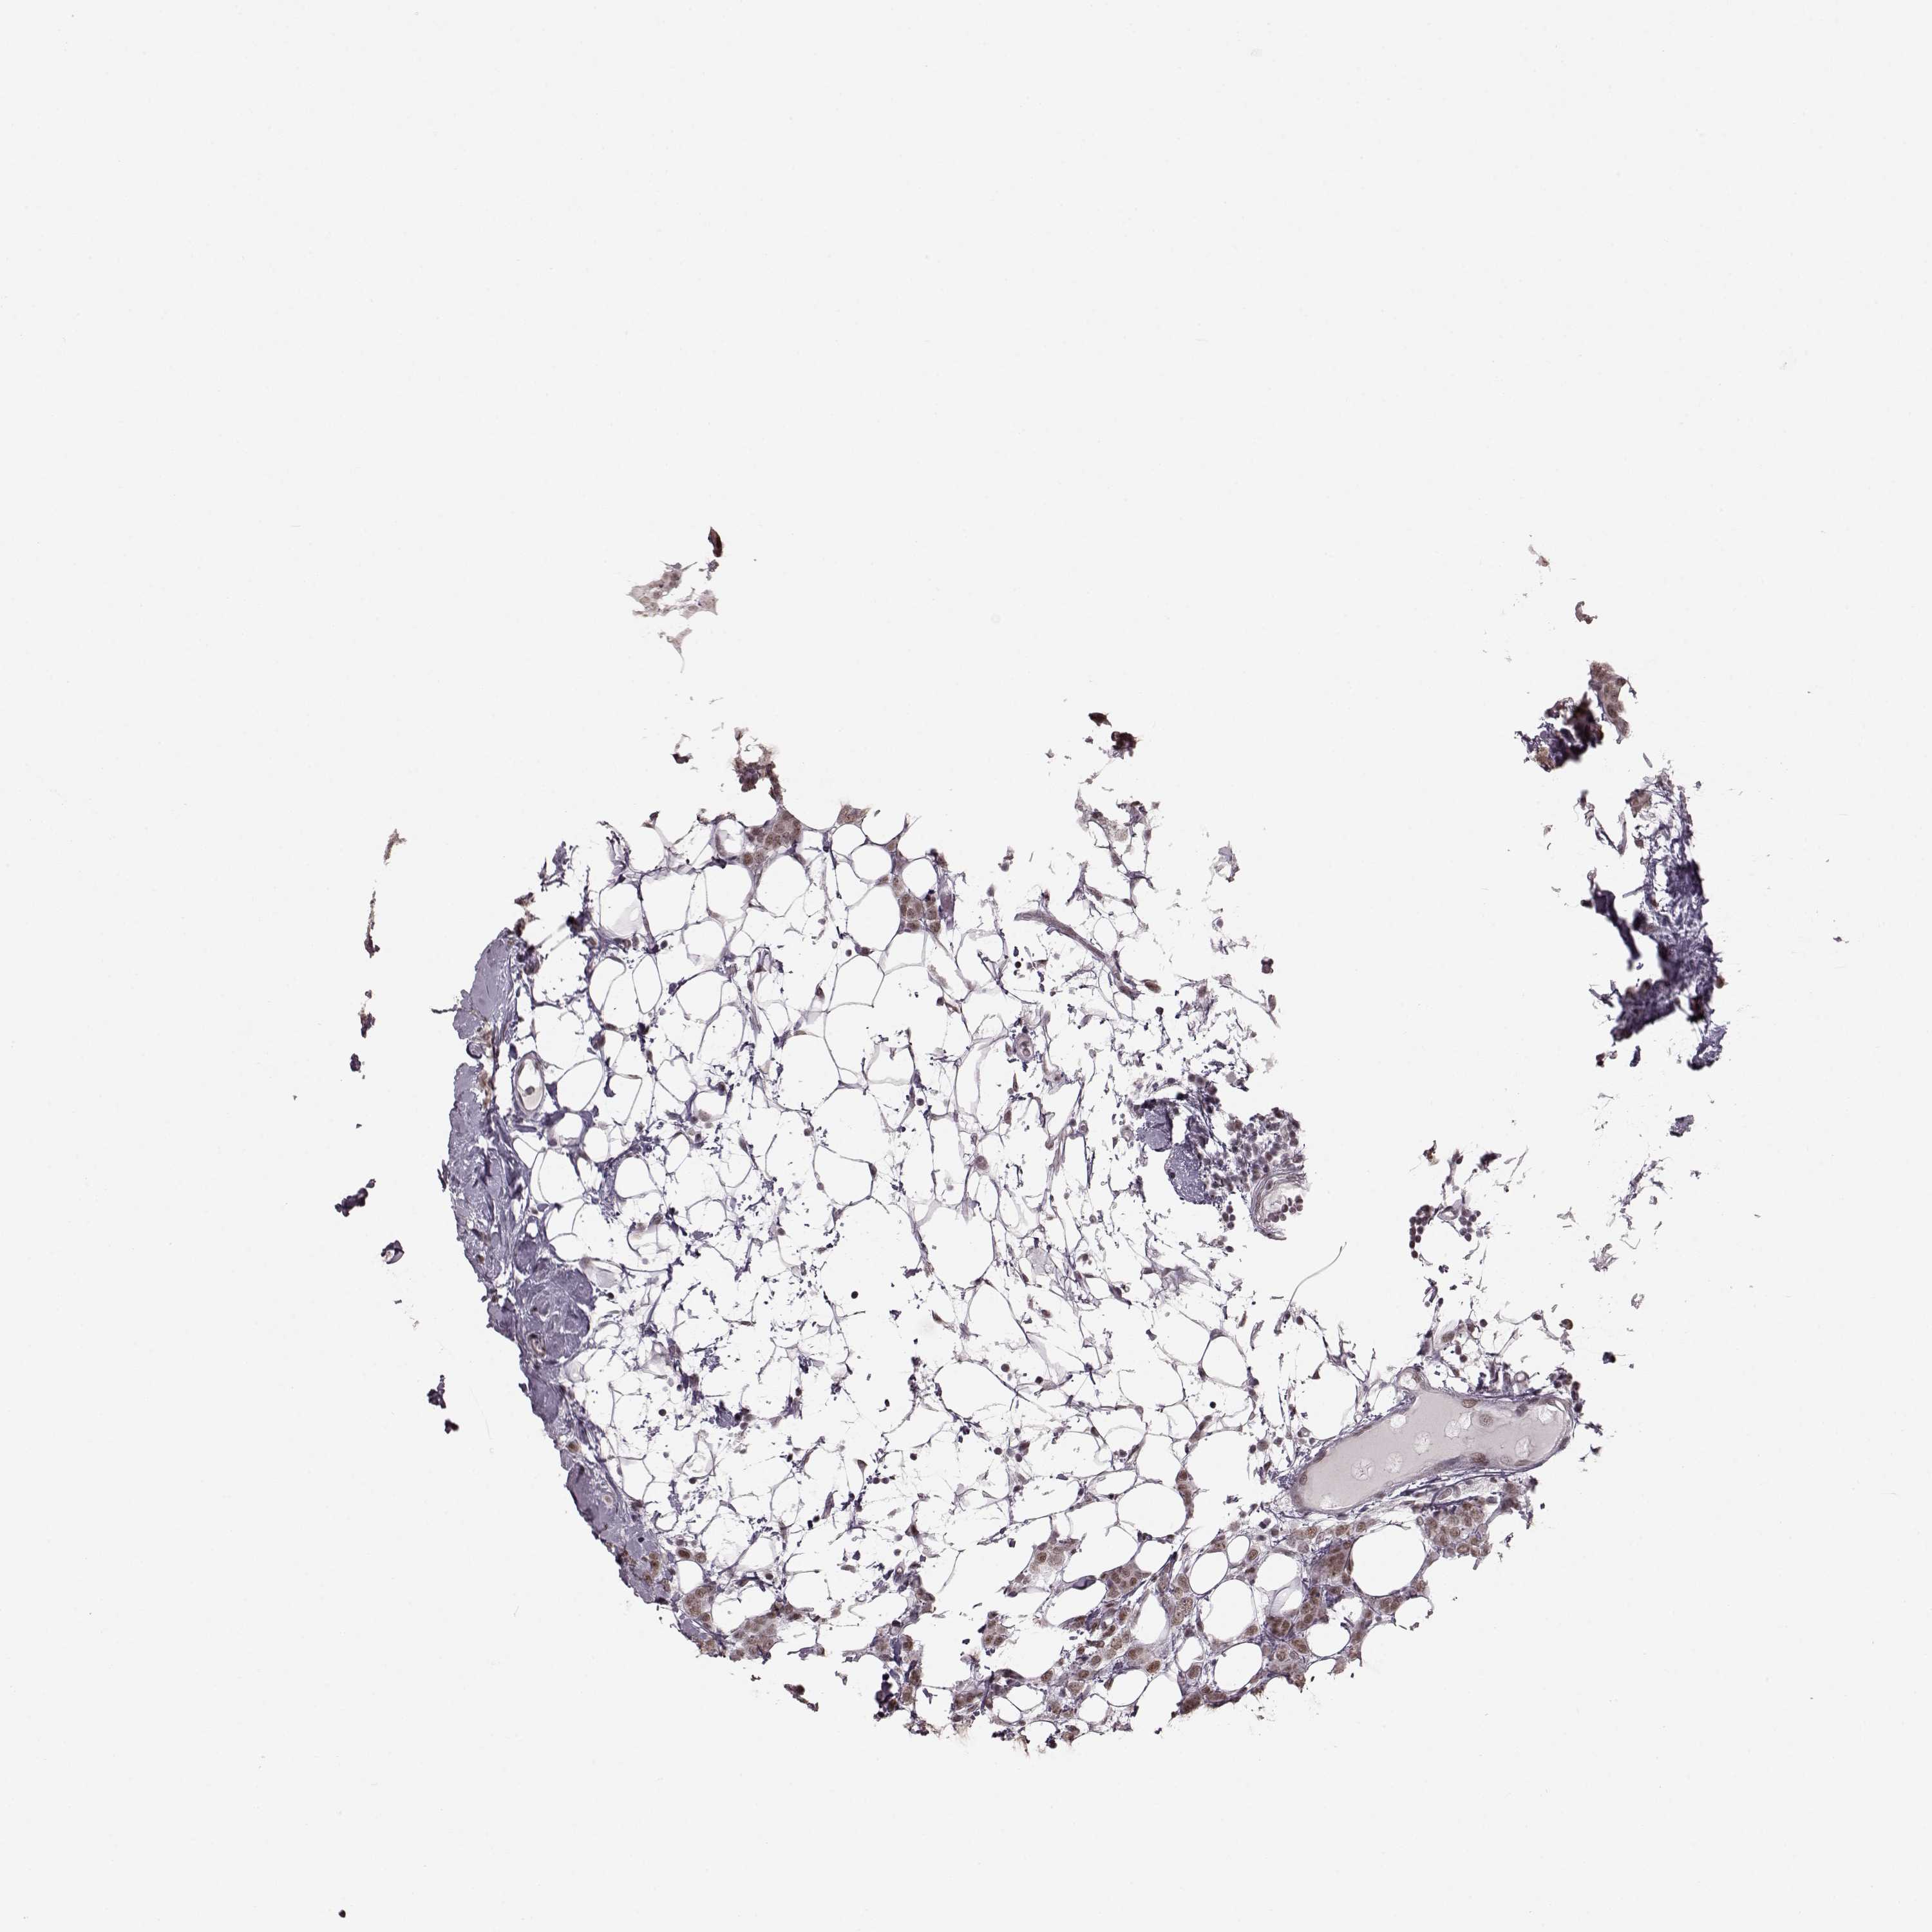

CANCER BREAST CANCER Show tissue menu

BRCA TCGA BRCA VALIDATION PROTEIN EXPRESSION